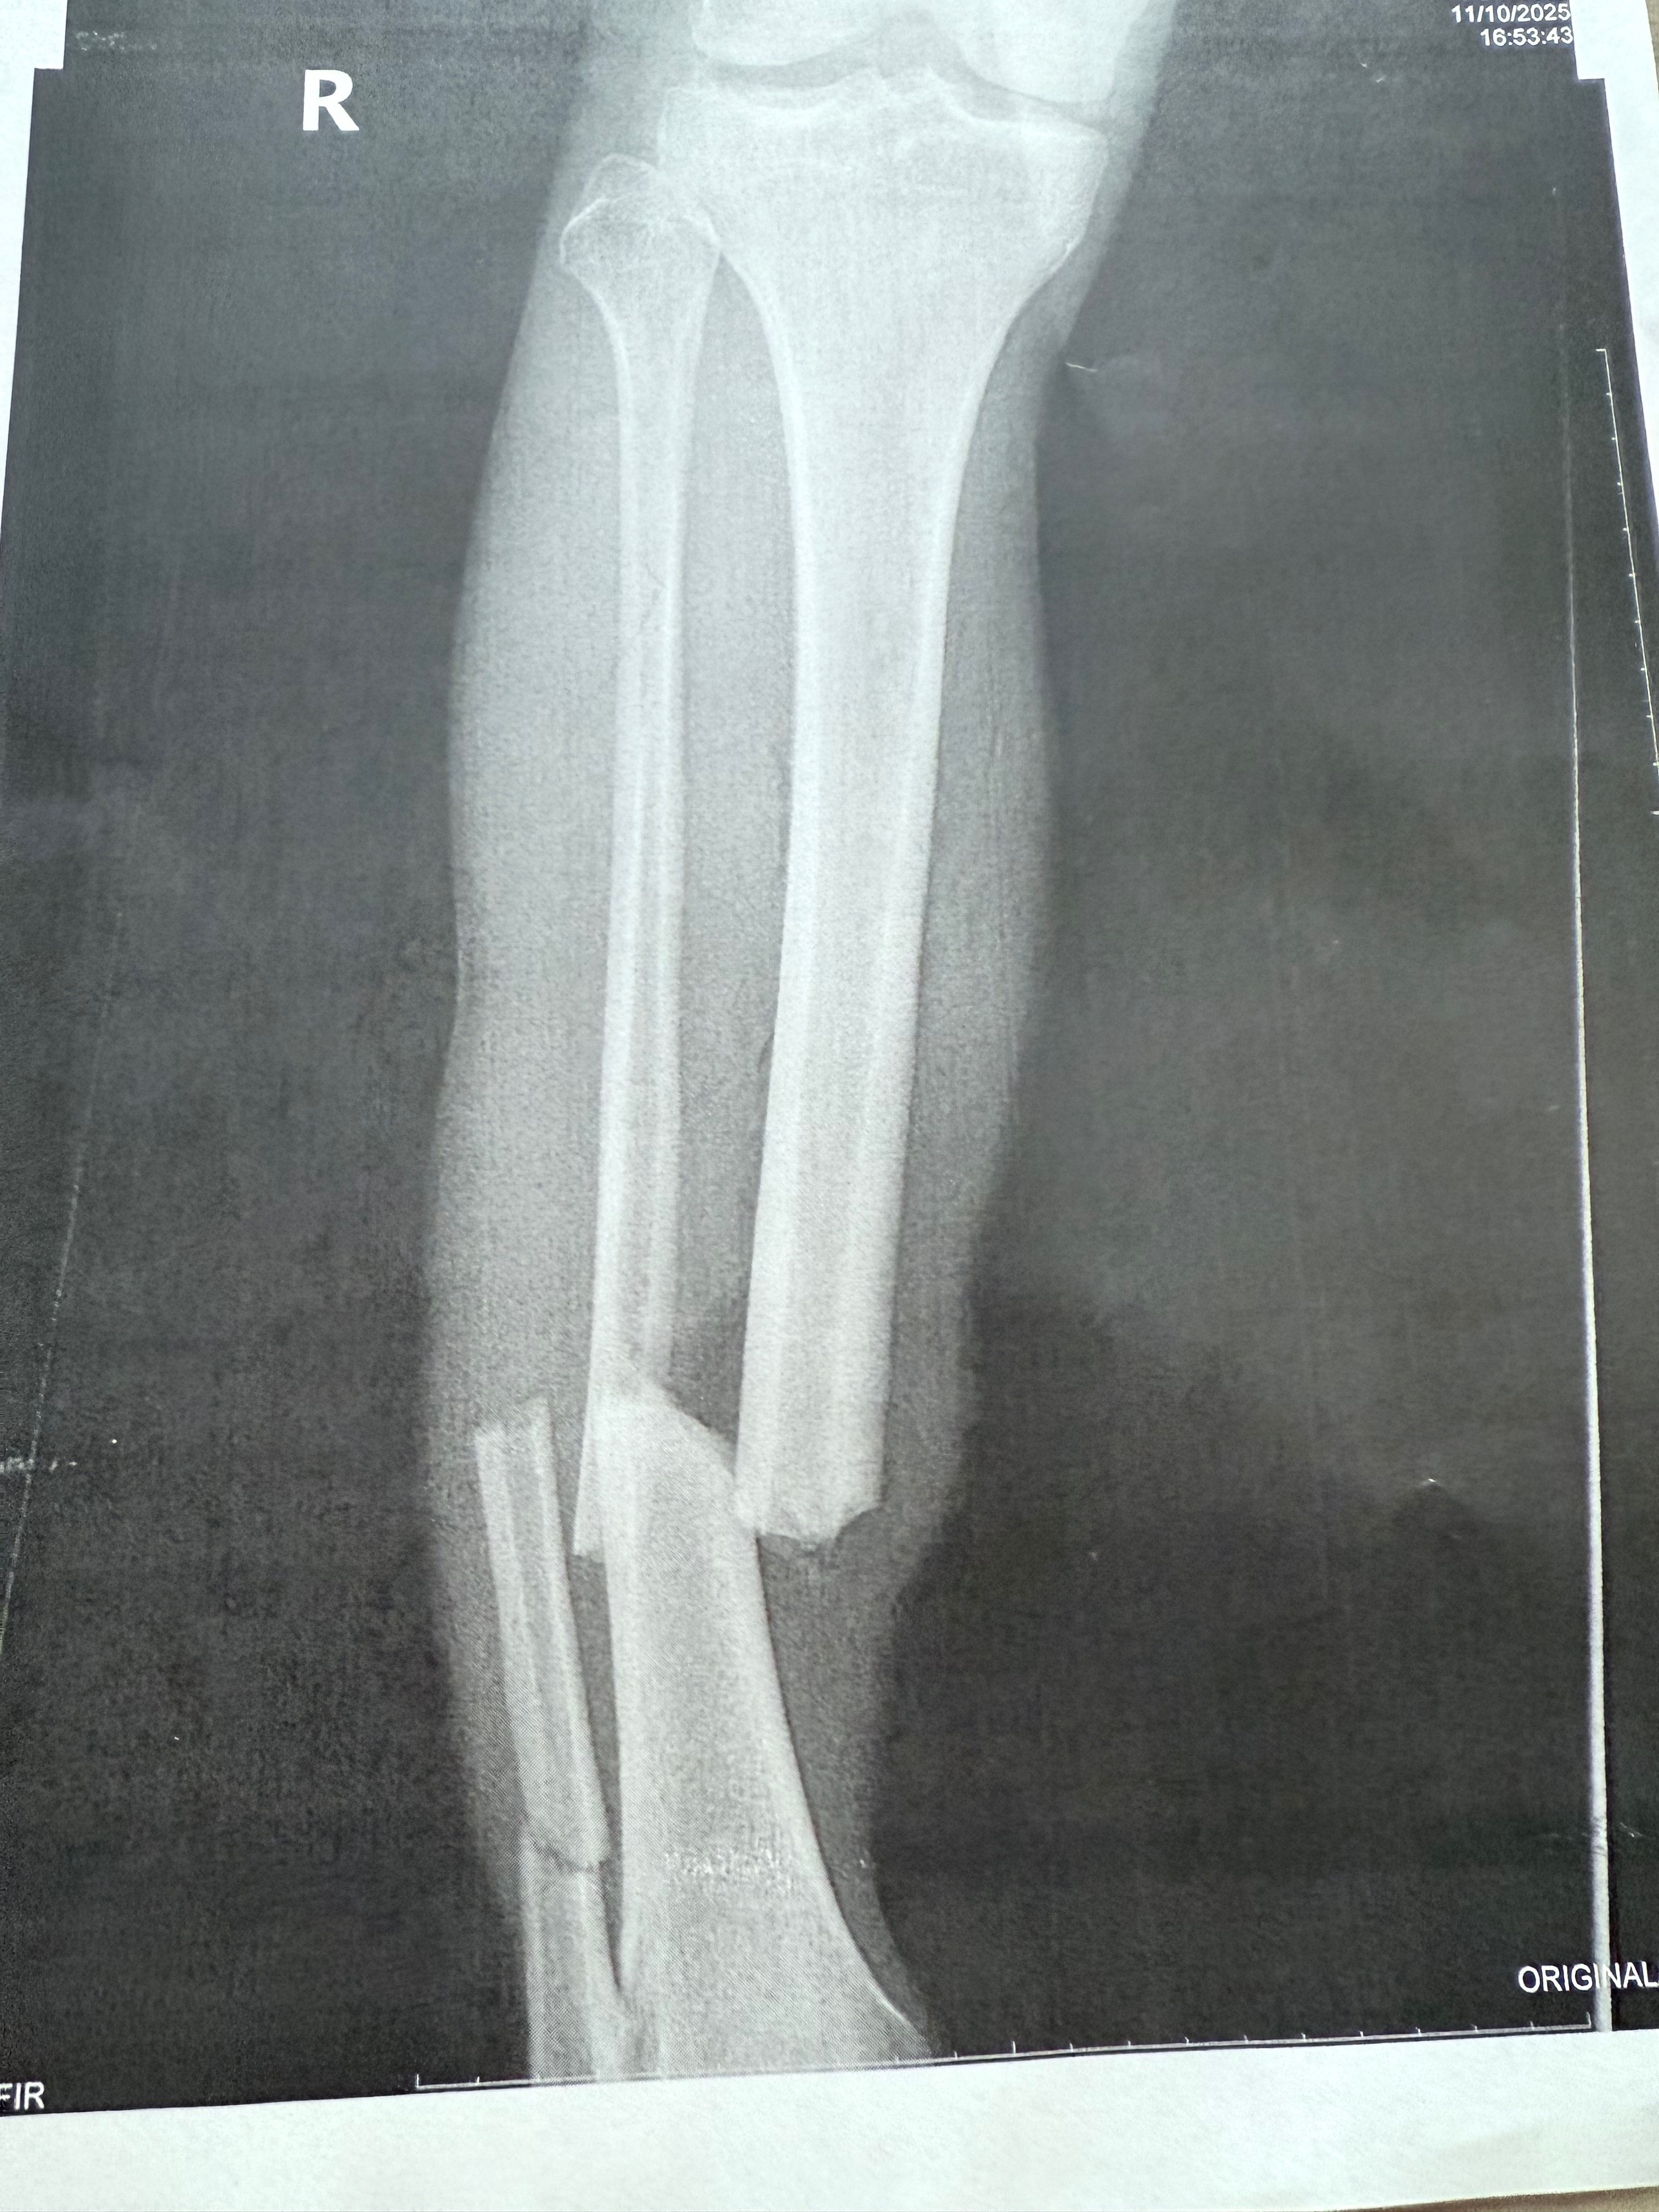

This GoFundMe is set up for Raymond. On 11/10/2025 at about 4:30 pm Ray was riding his bike home & an uninsured driver hit Ray with his car. The man stayed & cooperated with police but told them he has no insurance to pay for any of this. Ray had to have surgery to repair his leg. He broke his tibia and fibula in 3 different spots.